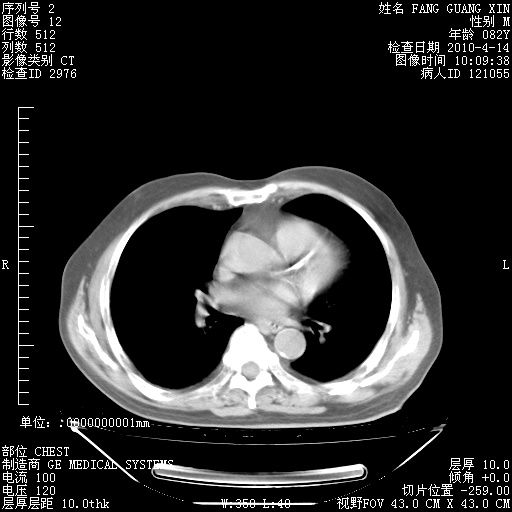

4月14日肺部CT

肺部CT平扫未见异常。